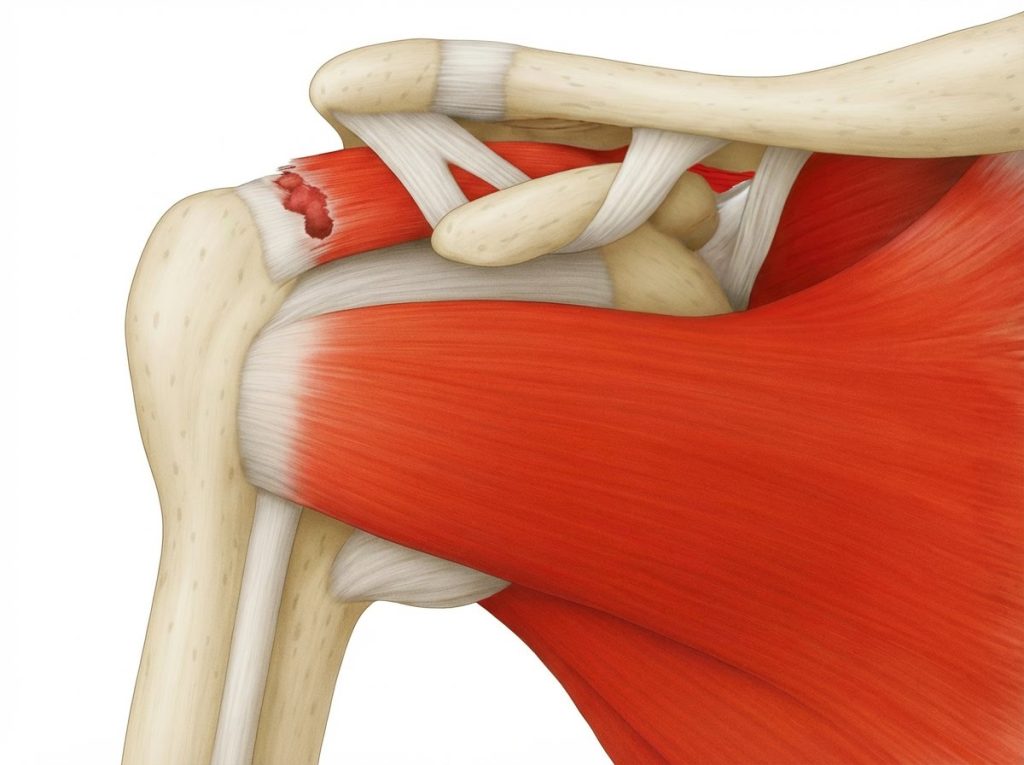

Symptomatische Rotatorenmanschettenruptur (Teil- oder Vollruptur)

• Beurteilung der Rupturform: partiell, vollständig, zurückgezogen, degenerativ, traumatisch.

• Mobilisierung der rupturierten Sehne (meist Supraspinatus, ggf. Infraspinatus/Subscapularis).

• Darstellung des Ansatzbereichs am Knochen (Tuberculum majus/minus humeri).